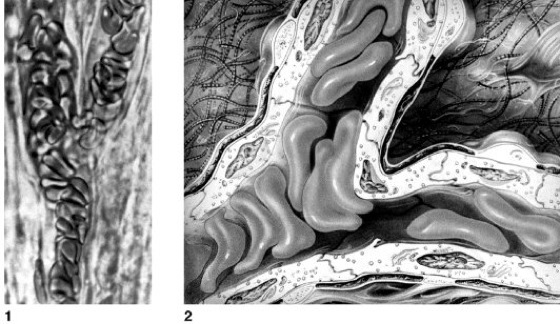

1 Rasterelektronenmikroskopische Aufnahme von Erythrocyten, die deren charakteristische, eingedellte Form sichtbar macht. 2 durch extremen Vitamin-E-Mangel verformte Erythrocyten; die Erythrocytenmembran weist unregelmäßige Ausbuchtungen auf. 3 durch Wasserentzug hervorgerufene Stechapfelform eines (geschrumpften) Erythrocyten.